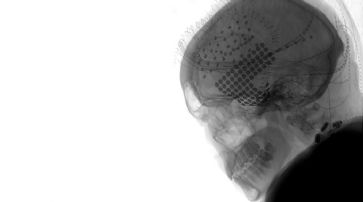

Die Röntgenaufnahme des Kopfes eines Versuchsteilnehmers zeigt die Platzierung von Elektroden über den frontalen (oben) und temporalen (unten) Regionen des Gehirns. /

2008 und 2015 wurde die Gehirnaktivität von 29 Patienten aufgezeichnet, die sich einer Epilepsieoperation unterziehen mussten. Während der Operation wurden den Patienten die Ohrstöpsel entfernt und ihnen der Song «Another Brick in the Wall, Part 1» von Pink Floyd vorgespielt. Die Forscher zeichneten die elektrische Aktivität von Hirnregionen auf, die auf Eigenschaften der Musik abgestimmt sind, wie Ton, Rhythmus, Harmonie und Worte.

Nun wurden diese Aufzeichnungen erneut mit neuer KI-Technik analysiert, um ein digitales Modell des Songs zu erstellen. Das Modell war in der Lage, den Song mit einer Genauigkeit von 80% zu rekonstruieren. Die Forscher konnten auch die musikalischen Elemente des Songs, wie Rhythmus, Betonung und Akzent, identifizieren. Ausserdem wurde bestätigt, dass die rechte Seite des Gehirns stärker auf Musik eingestellt ist als die linke Seite.